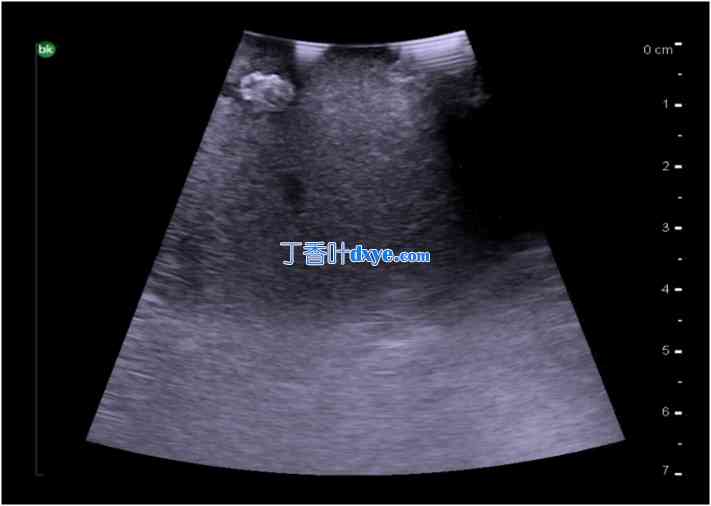

图 14

术中门静脉血流多普勒超声检查。

15.jpg